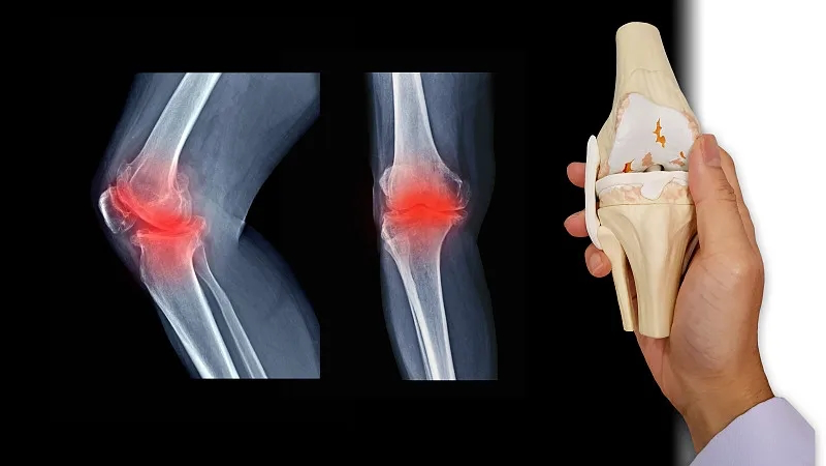

膝骨关节炎(KOA)是一种膝关节退行性疾病,其病理特征为滑膜炎症、骨质增生、骨赘形成及关节软骨的逐渐丢失,进而引发关节疼痛、肿胀、畸形和活动受限等临床症状[1-2]。若长期不治疗,KOA可能会造成关节功能丧失,严重影响患者的生活质量[3-4]。目前临床常用的治疗方式包括非药物治疗、药物治疗、手术治疗等[5-7]。上述治疗手段主要致力于缓解疼痛、改善关节功能以及延缓KOA的进展,并不能彻底修复关节软骨的损伤,且患者可能需要面临多次手术治疗,无疑加重了其经济负担[2-3]。